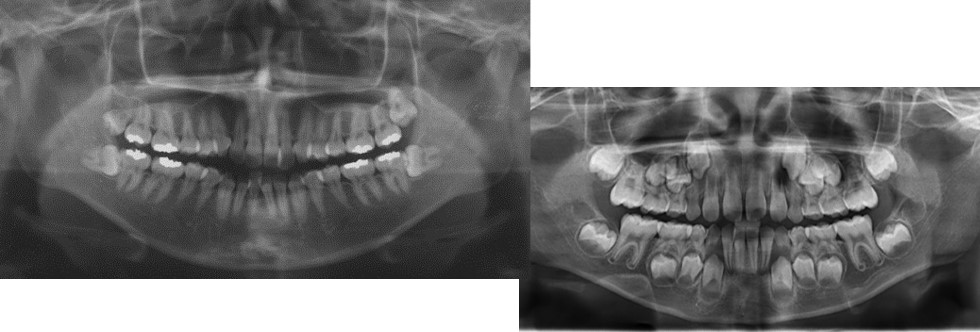

矯正の検査って何をするの? 何がわかるの? ~矯正治療前の精密検査

30代からの歯列矯正 ルーセント歯科にて歯型とレントゲンを撮る 1回目

ワイヤー矯正ブログ加藤編